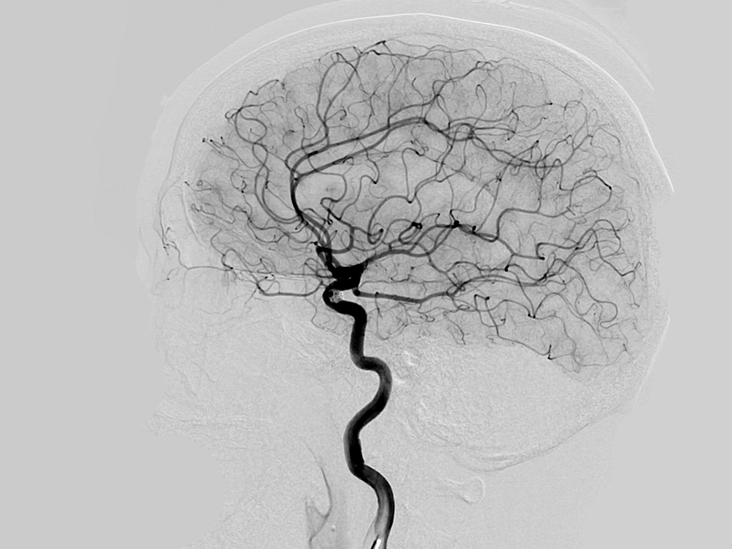

(Angiogram)

هو تشخيص للأوعية الدموية ومشاكلها من انسدادات وتضيقات وتشوهات.